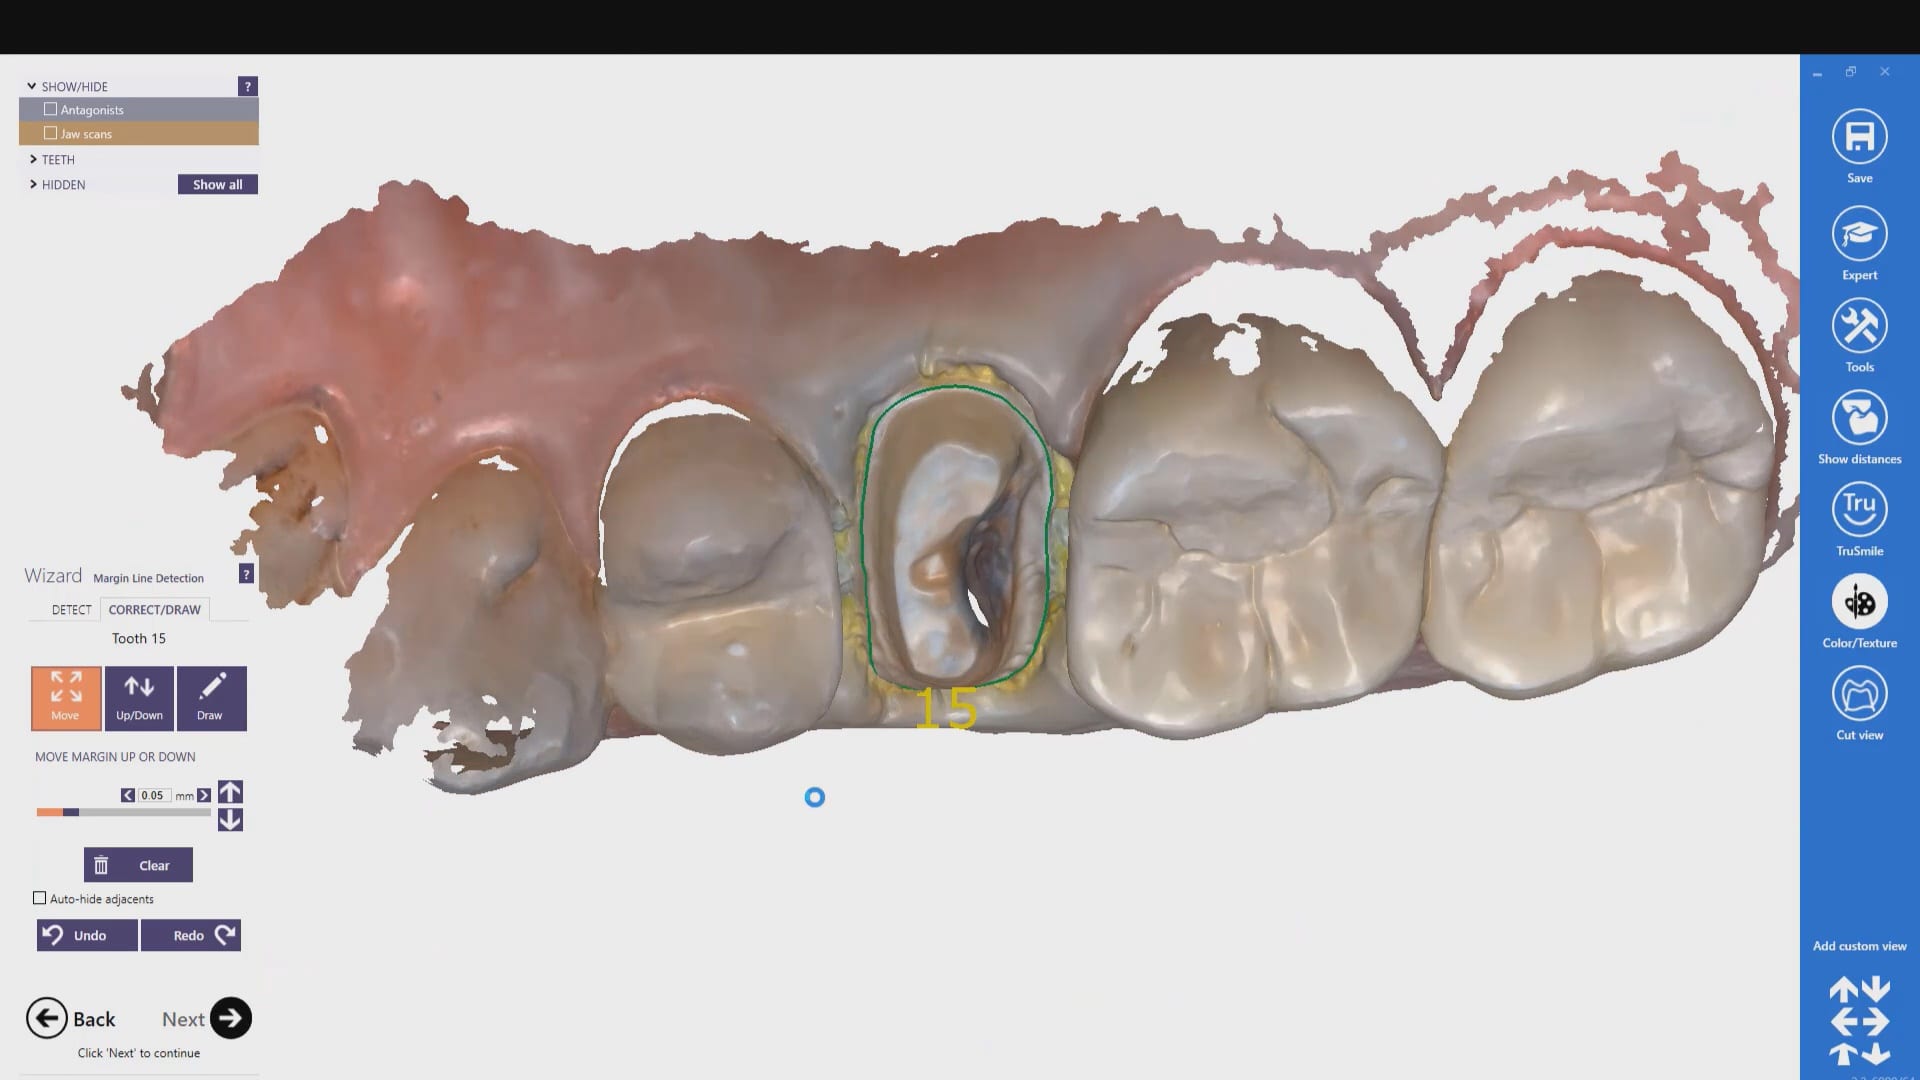

With Meditlink software, you have the option of designing the case yourself or sending it off to your partnered lab. The following video shows what happens to your case once the lab downloads the case

In this particular case, we designed our own crown and milled it with the coritec one milling machine